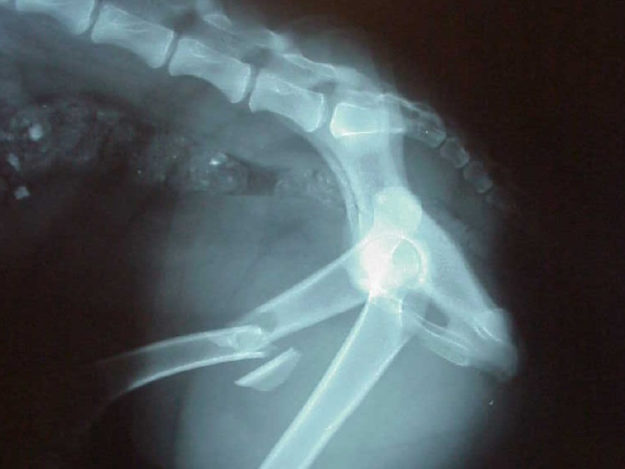

A proptosis refers to a sudden protrusion of the globe from the orbit. While they can appear quite scary, with some preparation they can easily be addressed. The number one question that you as a practitioner need to determine, is should the globe be replaced or should an enucleation occur.